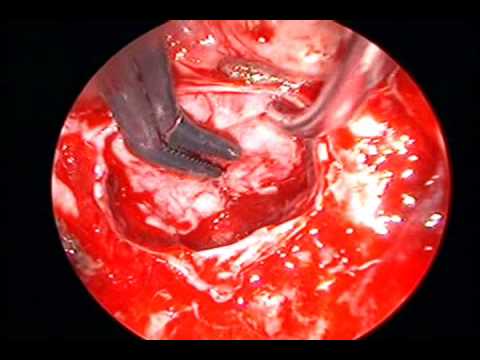

Tętniak tętnicy łączącej tylnej

Doktor Pakzaban prezentuje mikrochirurgiczny zabieg klipsowania tętniaka tętnicy łączącej tylnej.